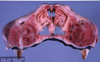

MDx? EDx? Etiology?

MDx: multifocal endocardial mineralization

EDx: uremic endocarditis

Etiology: renal diease - nonrenal lesion